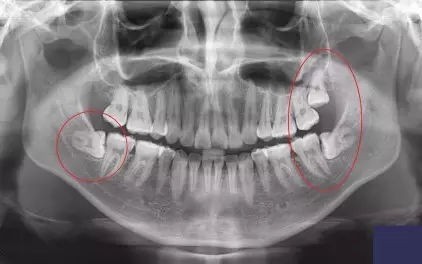

大部分智齒部分或全部躲在牙齦下,肉眼根本看不見,只能透過X光片看到。

比如這樣:

(肉眼無法看見的3顆智齒,X光下清清楚楚)